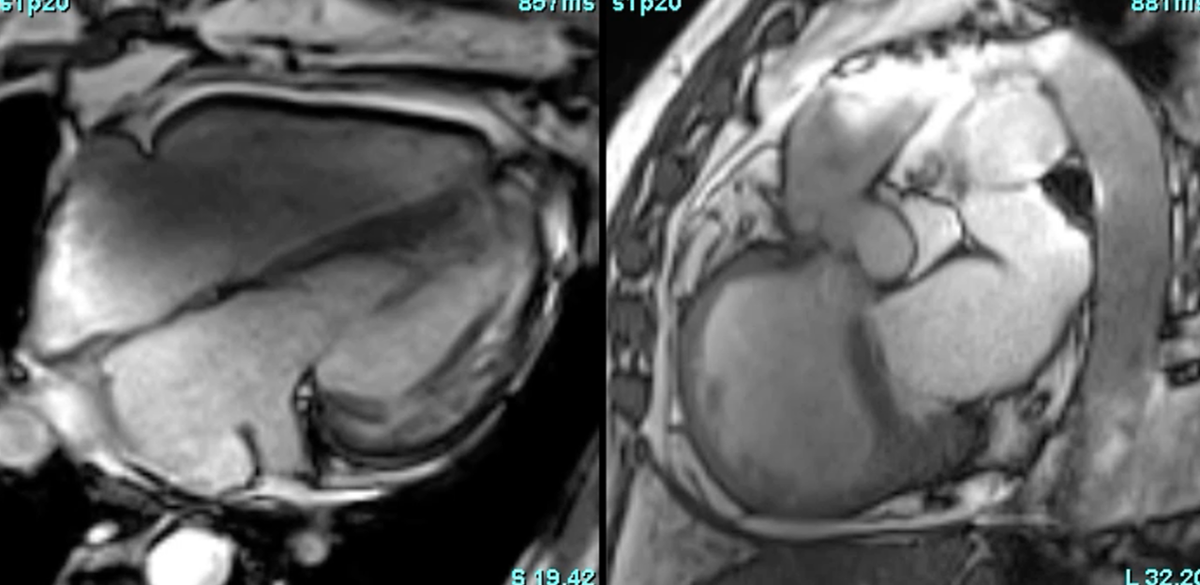

CMR in CCTGA